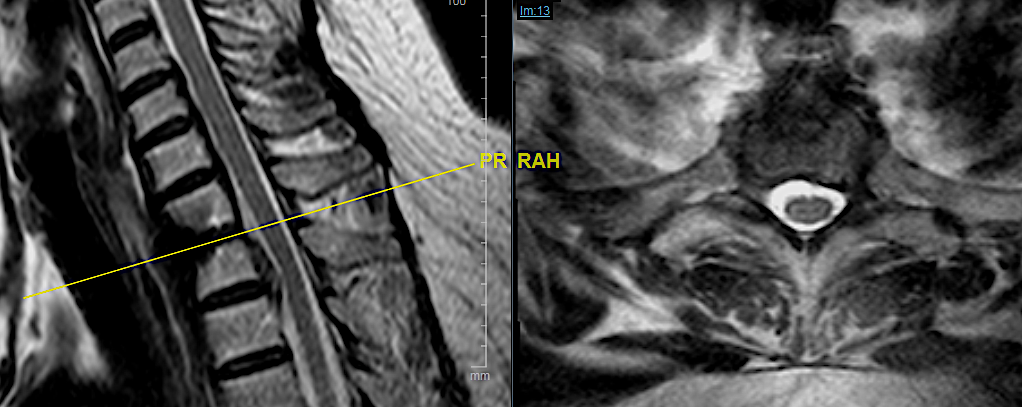

CASO CLÍNICO 2: HERNIA DISCAL C7-TH1 ASOCIADA A ESTENOSIS DE CANAL

Paciente de 46 años que consulta por clínica de mielopatía cervical de evolución progresiva en los últimos dos meses. Tuvo una braquialgia derecha 4 meses antes que mejoró con tratamiento conservador.

Este caso me parece interesante porque hubiese podido ser tratado por vía posterior al ser una hernia lateral, sin embargo, no se trataba de una afectación segmentaria aislada sino que en la misma RM podía apreciarse estenosis de canal en C6-C7 con compresión medular a dicho nivel. No hay que olvidar que el motivo de la consulta fue la instauración de una mielopatía cervical progresiva (inestabilidad, urgencia miccional e hiperreflexia) pues la braquialgia derecha estaba en proceso de remisión.

Por las razones expuestas, a pesar de un thoracic inlet angle bastante alto, opté por realizar un abordaje anterior con descompresión + artrodesis IS con cajas atornilladas C7-Th1.

La evolución clínica fue favorable. En la RX control lateral apenas podemos visualizar la caja inferior sin embargo, por la ausencia de dolor, por la falta de edema en STIR en cuerpos vertebrales C7-Th1 y por la resolución de la clínica neurológica no considero imprescindible por ahora, someter al paciente a un TC cervical (gran radiación en paciente joven).